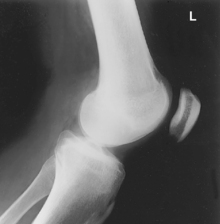

• Prone, knee centered to CR and midline of table or IR

• If patella area is painful, place pad under thigh and leg to prevent direct pressure on patella.

• Rotate anterior knee approximately 5° internally or as needed to place an imaginary line between the epicondyles parallel to the plane of the IR.